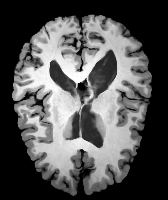

Image Manual Seg DA-1 Mono-21 DA-21 Mono-65 Refer to caption Refer to caption Refer to caption Refer to caption Refer to caption Refer to caption

Figure 2:  Examples of knee MRI registration (top) and brain MRI segmentation (bottom) results. Top: The first two columns are the moving image/segmentation and the target image/segmentation followed by the warped moving images (with deformation grids)/segmentations by different models. Bottom left to right: original image, manual segmentation, and predictions of various models. Mono-i𝑖i and DA-i𝑖i represent the mono- and DA models with i𝑖i manual segmentations respectively.

Image Manual Seg DA-1 Mono-5 DA-5 Mono-200 Refer to caption Refer to caption Refer to caption Refer to caption Refer to caption Refer to caption

Figure 4: Examples of brain MRI registration (top) and knee MRI segmentation (bottom) results. Top: The first two columns are the moving image/segmentation and the target image/segmentation followed by the warped moving images/segmentations by different models. Bottom left to right: original image, manual segmentation, and predictions of various models. Mono-i𝑖i and DA-i𝑖i represent the mono- and DA models trained with i𝑖i manual segmentations respectively.